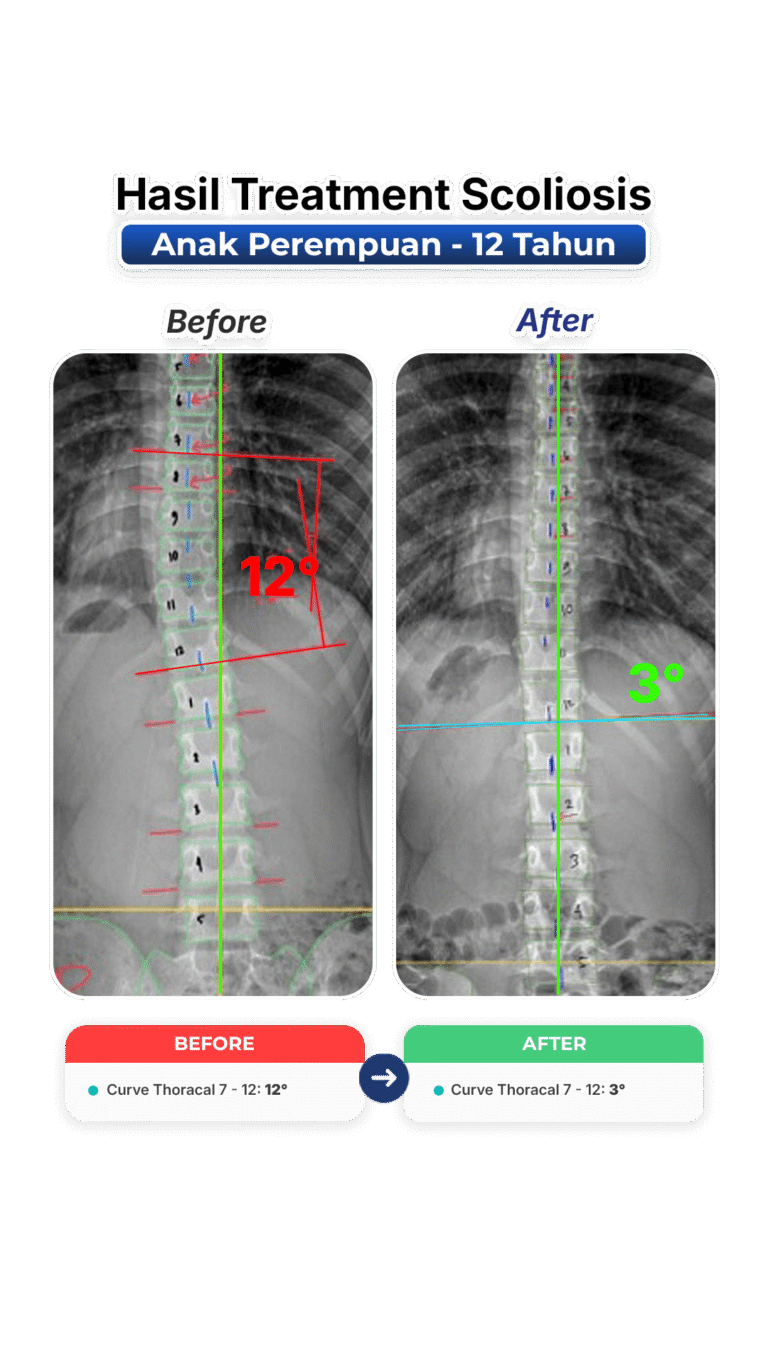

Perubahan nyata setelah mengikuti program terapi skoliosis di VLife Medical Galaxy Mall 3.

Perawatan scoliosis dilakukan melalui evaluasi tulang belakang menyeluruh, program terapi bertahap, fokus keseimbangan postur, mengurangi nyeri, memperlambat progres kelengkungan, serta meningkatkan fungsi gerak harian pasien secara aman dan terkontrol medis.

Penanganan skoliosis berbasis evaluasi postur menyeluruh, terapi manual khusus, latihan koreksi, serta pemantauan progres di setiap sesi. Dibuat untuk remaja dan dewasa yang ingin mengendalikan kelengkungan skoliosis dan mengurangi nyeri.